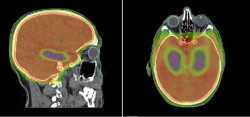

El Servicio de Oncología Radioterápica del Hospital del Mar de Barelona ha coordinado un estudio que demuestra que proteger el hipocampo de la radiación en aquellos pacientes con cáncer de pulmón de células pequeñas que tienen que someterse a radioterapia para evitar la aparición de metástasis en el cerebro es una "estrategia válida" para proteger su memoria sin afectar sus probabilidades de supervivencia.